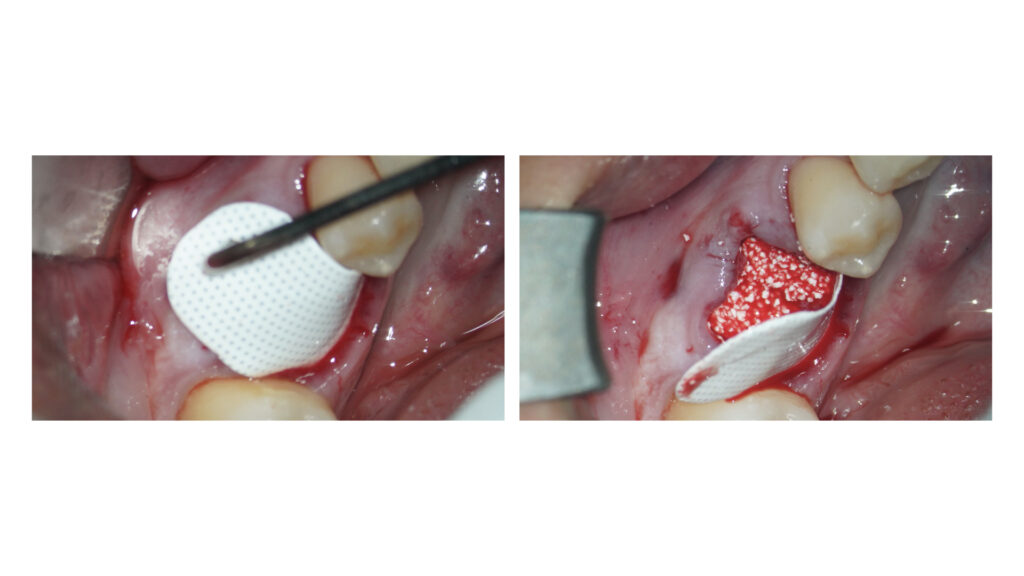

インプラント治療に向けたGBR(骨増成)およびソケットプリザベーションをCytoplast TXT-200を用いてオープンバリアメンブレンテクニックにて行いました。

メンブレン設置に向けてエンベロープ形成を事前に行なっています。

今後2週間程度でメンブレンを除去して、インプラント手術を1ヶ月後に予定しています。